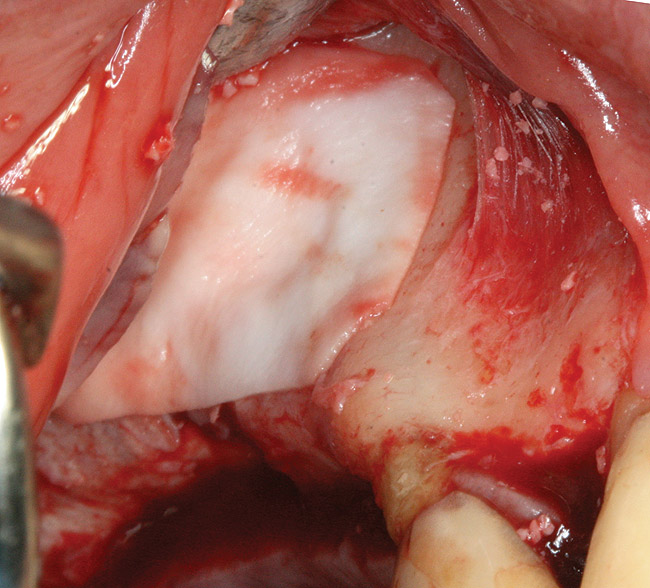

The technique described below is based on a deep buccal full-thickness flap with vertical release in the canine area, followed by creation of a “window” at the lateral wall of the sinus (Figure 2). The bony window is either removed or rotated medially with the sinus membrane and pushed inward. The Schneiderian membrane is then separated from the bone anteriorly, posteriorly, and medially until clinically sufficient space is established (Figure 3). The created space, which occupies the lower third of the sinus, is filled with a bone graft (Figure 4), and the lateral access window is covered with a collagen membrane (Figure 5).

Fig 3. Schneiderian membrane from the sinus walls is elevated.

Figure 3

Fig 4. Space is created between the Schneiderian membrane and the sinus walls filled with particulate xenograft.

Figure 4